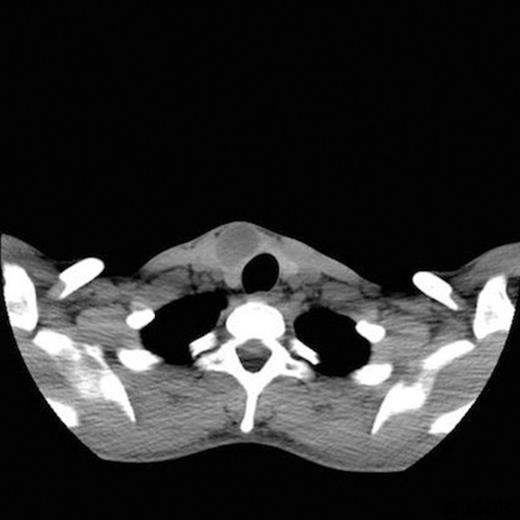

A 25-year-old man presented to the otolaryngology department with a one-year history of a asymptomatic, anterior triangle neck swelling which he had incidentally noticed. On examination, there was a 3×2cm swelling just right of the midline which moved with swallowing. There was no neck lympadenopathy. The remainder of ENT examination was unremarkable with nasendoscopy showing normal cord movements. Biochemically, he was euthyroid. The general practitioner had organised an ultrasound that showed a 33×26x19mm complex cyst in the right lobe of the thyroid gland. A fine needle aspiration (FNA) was performed and a non-contrast CT scan was requested. The FNA was reported as Thy1; a subsequent ultrasound guided FNA also was reported as Thy1. The CT scan showed a cystic lesion (figure 1) which seemed to be arising from the right lobe of the thyroid gland. Treatment options were discussed and he was listed for a diagnostic right hemithyroidectomy.

Schwannoma of the ansa cervicalis is extremely rare and there have only been four reported cases in the literature. They are notoriously difficult to diagnose as history and clinical examination are non specific. In the head and neck, these tumours are often mistaken for other lesions such as enlarged lymph nodes, carotid body tumours, branchial cysts, or thyroid lesions (2,3). Imaging in the form of CT scan and MRI are helpful in providing some suspicion of a schwannoma (4). On CT, schwannomas appear as well-defined homogeneous masses which show cystic change with contrast enhancement that become more prominent as the lesion enlarges (5). On MRI scans they are well-circumscribed homogenous masses that exhibit high-signal intensity on T2-weighted images and a relatively homogenous low-signal intensity on T1-weighted images. FNA is highly suspicious of schwannoma if spindle cells are isolated. However, diagnosis is only definitively established by histopathological examination of the tumour. This classically shows the pattern of Antoni A and Antoni B cells in addition to Verocay bodies (6).

In our case, preoperative imaging has suggested thyroid pathology therefore the intra-operative findings were unexpected. The preoperative CT did not have contrast enhancement as thyroid malignancy was a differential diagnosis. The blood filled cavity of the lesion was presumably due to the previous FNAs. The position of the schwannoma between the strap muscles was consistent of the nerve of origin being a branch of the ansa cervicalis.